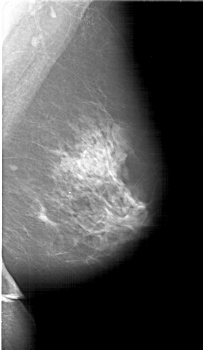

A_1913_1.RIGHT_MLO

RIGHT_MLO LINES 6286 PIXELS_PER_LINE 3646 BITS_PER_PIXEL 12 RESOLUTION 43.5 NON_OVERLAY